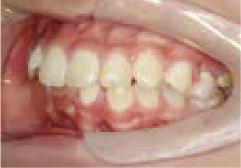

受け口

下の歯が前に出る“受け口”の治療

Yさん (矯正開始時:7歳)

Before

After

下あごが前に出ていて、上あごの成長が少ない状態でした。他の歯科では将来あごの手術が必要と言われましたが、手術をせずに治したいという思いで、口コミを見て当院に来られました。

治療を終えて

装置を使うことで奥歯の高さが上がり、かみ合わせ全体が整うことで、前歯のズレも改善されました。さらに舌が正しい位置にくるよう舌を持ち上げるトレーニングを行いました。外科的手術はせず、非抜歯で治療完了しました。

主訴・治療内容 他院で将来あごの手術が必要と言われたが、できれば手術をせず治したいという思いで、口コミを見て当院へ相談に来られました。

治療期間 5年

費用 495,000円(税込)